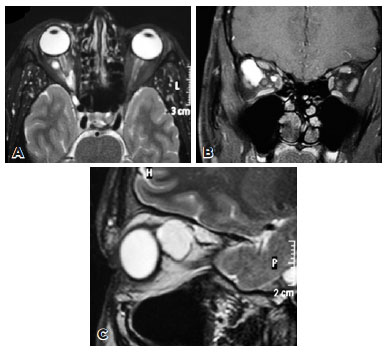

A 30-year-old male presented to the University Hospital of Ribeirão Preto for a follow-up examination after having undergone lateral orbitotomy elsewhere 2 years ago. According to him, the procedure had been performed to treat right eye proptosis, secondary to a large orbital mass. His past medical history was significant for multiple steroid injections into the right orbit for the management of a presumed orbital hemangioma during childhood. Examination of the right eye revealed no proptosis and unrestricted ocular motility. The funduscopic and visual field examinations were normal. Magnetic resonance imaging (MRI) showed multiple, large intraconal cysts in the right orbit. T1- and T2-weighted MRI revealed well-circumscribed masses around the right optic nerve with high signal intensity compared to the vitreous on T1W and T2W images (Figure 1). Histopathological evaluation of the sections of specimen obtained from the previous orbital surgery revealed ducts and acini of benign LGT (Figure 2) and absence of atypical cells, mitotic activity, and necrosis. No further intervention was planned as the patient was asymptomatic.